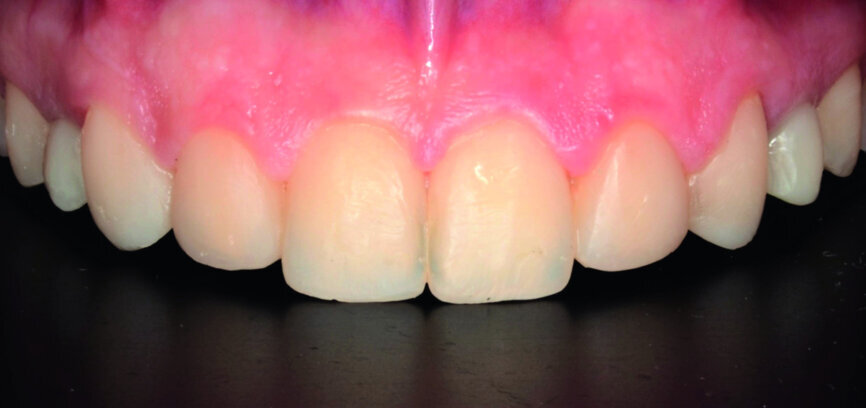

- Dental proportions: the width of wellproportioned teeth should be approximately 60 % to 75 % of their height (Fig. 3).

At the end of orthodontic treatment, gingival margins were well aligned, midlines were centred and canines and first premolars were positioned to facilitate the restorative phase of treatment (Figs. 34–36). At this phase, a final CR mounting and wax-up was performed (Figs. 37–39), as well as the anterior teeth restorations (Fig. 40).

Orthodontic treatment has improved both dental and facial aesthetics (Figs. 41–47) and the functionality of the occlusion (Figs. 48–52).